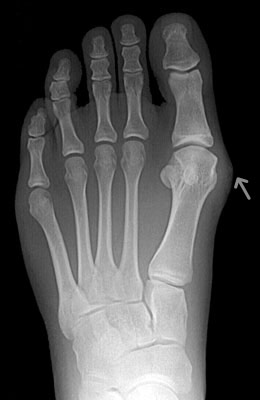

Osteotomy Bunionectomy, Hammertoe Correction and Plantar Plate Repair after

Osteotomy Bunionectomy, Hammertoe Correction and Plantar Plate Repair

Ziba is a 67-year-old female with years of foot pain. Her bunion was so severe she had placed a lot of weight on her 2nd and 3rd toes which had become totally dislocated (as shown in x-rays). Ziba required an osteotomy bunionectomy, hammertoes corrections with our Ossio™ implant and metatarsal phalangeal joint relocation and plantar plate repair. Ziba was allowed to place weight on her foot right after surgery and was back in shoes at 8 weeks. An amazing result considering how difficult toe relocation can be. After picture taken immediately following surgery.